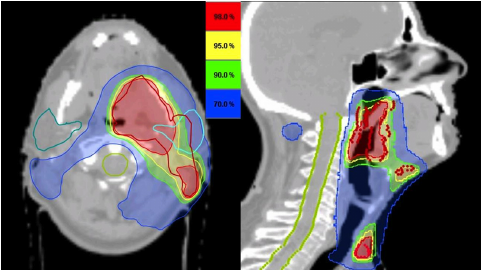

RT in head and neck cancer - SE

Worst SE - intensive mouth care needed

Held in place by thermoplastic shells

SE: skin reaction, fatigue, mouth soreness, difficulty swallowing, voice changes, hair loss, tinnitus Long term risk of tooth decay, hearing changes, difficulty swallowing + xerostomia (dry mouth)

What is the GTV, CTV + PTV?

GTV = gross tumour volume CTV = clinical target volume (margin has been added) PTV = Planning target volume (added margin due to patient + tumour movement)